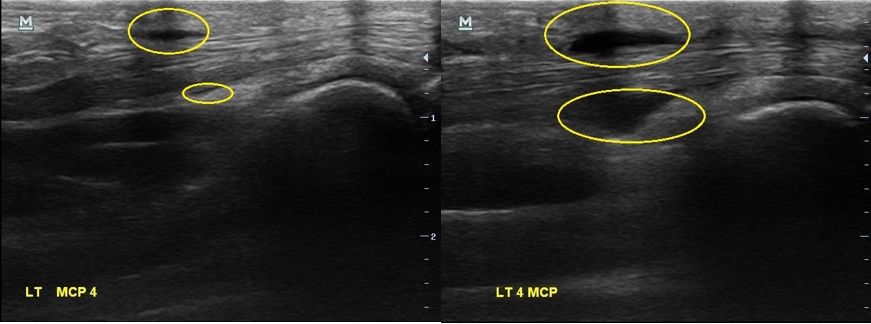

X-ray 검사상에는 특별한건 보이지 않습니다. 초음파 검사에서는.... 4번째 손가락을 굽혀주는 힘줄(4th flexor digitorum tendon)에 염증이 생겨있습니다.

2주 전보다 힘줄에 염증이 훨씬 심해져 있었습니다. 그리고

이번에는 한 부위만이 아니라 손가락 굽힘 힘줄을 따라 전체적으로 염증이 퍼져있습니다.

2주만에 비포 & 애프터

나 : 2주만에 염증이 엄청나게 심해졌네요... 보이시죠?